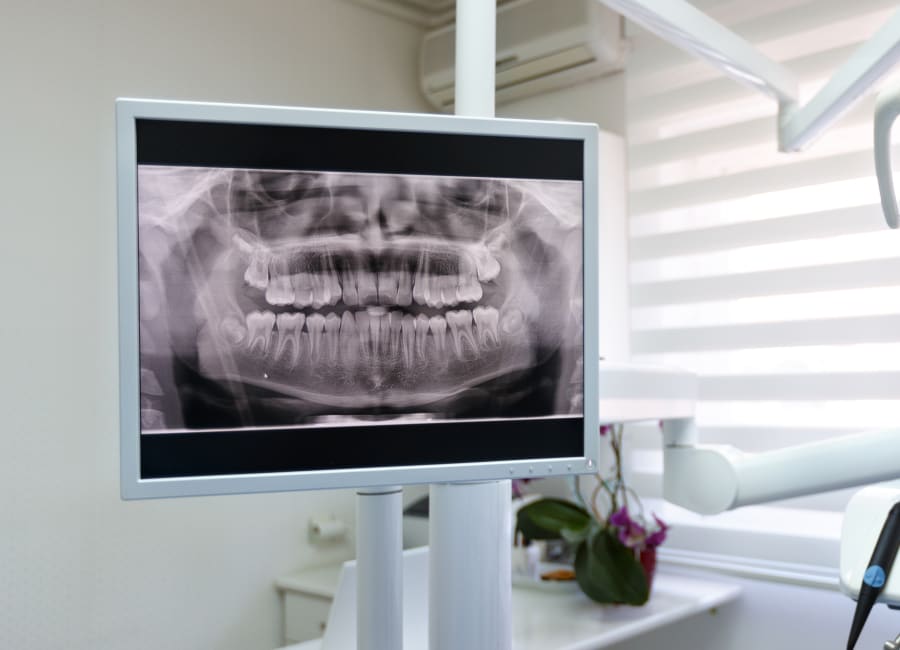

Panoramic X-rays

Panoramic X-ray technology allows your orthodontist to capture a single two-dimensional image that shows all of your mouth's oral structures. This image includes the teeth, the upper and lower jaws, and the surrounding structures and tissues.

Panoramic X-rays are crucial for assessing the presence or absence of specific teeth and their roots, their form and structure, their eruption sequence, and their relationship to one another in the jaws. This provides key insights for treatment planning and assessment.